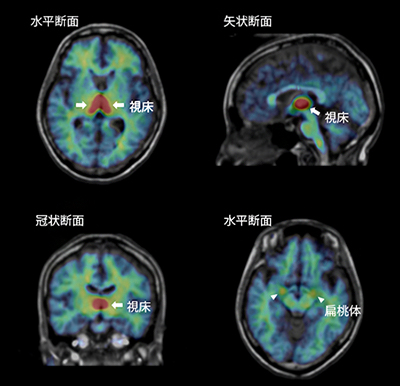

図 男女ともに視床(黄の部分)での脳内アロマターゼ量が高い人は、協調性スコアが低い

図1 アロマターゼのヒト脳での分布

[11C]CetrozoleによるPET撮像で得られた典型的な画像(女性)。アロマターゼの局所的な濃度を示す[11C]Cetrozoleの高い集積を暖色系の疑似カラーで表現し、MRI画像(モノクロ)と重ねた。視床、扁桃体などに高い集積が見られる。

図3 脳内アロマターゼ量と協調性に関連がある脳部位

脳内アロマターゼ量と協調性スコアの相関を統計的な手法を用いて解析した結果、男女ともに視床におけるアロマターゼ量が高いほど協調性が低いことが分かった。左グラフ上の赤点は、女性被験者を、青点は男性被験者を示す。この相関が最も高い(T値が大きい)領域を、右図のMRI画像の上に示したのが黄色〜白色の部分(視床)である。

また、男性・女性ともに視床におけるアロマターゼ量と協調性に関連が見られ、男性・女性とも視床のアロマターゼ量が多いほど協調性が低いことが示されました(図3)。これらの結果から、ヒトの性格と脳内のアロマターゼ量の関連性には、性差があるものと両性共通のものがあることが分かりました。